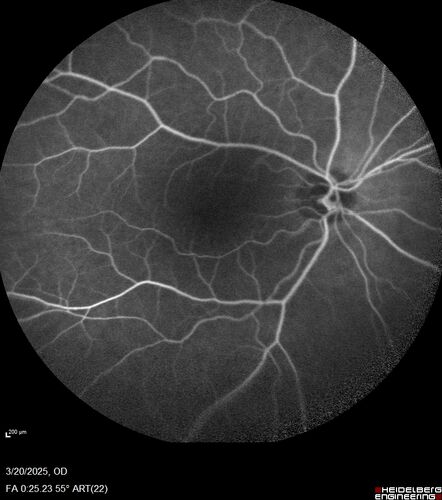

Paclitaxel induced cystoid macular edema - reversed when chemo stopped

74 year old retired physician  About 2-3 weeks ago there was gradual vision loss in the right eye. The patient was seen by an ophthalmologist who saw macular swelling and injected vabysmo. He has been on chemotherapy (Carbiplatin and Carboxytaxol for 2 cancers - advanced prostrate diagnosed 2019 - has had brain surgery AND squamous lung cancers treated with radiation)

Medical Hx: Prostate cancer (Onset: 2018). Pulmonary and bone cancer metastatic. Brain cancer metastasized from prostate cancer.

Surgical Hx: Right frontal & Frontoparietal Craniotomy (Onset: 2024). Appendectomy. Hemorrhoidectomy. Herniorrhaphy. Prostate. Systemic Meds: Chemotherapy. Radiation. Eligard Every 3 Months 22.5 MG per 0.375 ML Prefilled Syringe. MIRALAX prn. Tums Freshers 500 MG Chewable Tablet. Vitamin D. XGEVA.

VA OD: Dcc20/125+1

VA OS: Dcc20/125-2

TP: OD:12 OS:15